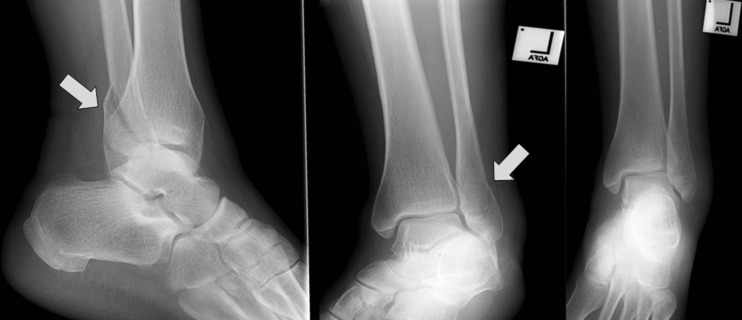

Fig. 2.

Three ankle trauma radiograph series. A minimally displaced lateral malleolus fracture is seen